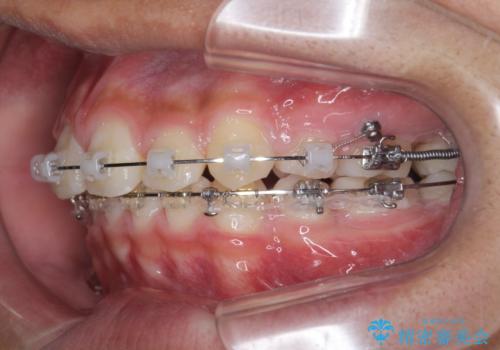

- 前歯のがたつきが原因で歯ブラシしづらい、見た目を改善したい!と矯正治療を希望され来院されました。

スペースの不足が見られるため、小臼歯の4本抜歯を行いマルチブラケットを用いた矯正治療を計画します。

噛み締めが強く、治療に時間がかかりましたが矯正治療の仕上がりに満足いただくことができました。